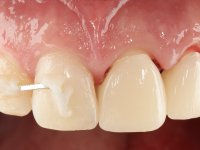

Foi feito o tratamento endodôntico dos dentes 2.1 e 2.2.de imediato, a sintomatologia que o paciente manifestava a isso impunha. Na mesma consulta foi realizada uma extensa gengivetomia com o bisturi elétrico, no sentido de expor os limites cervicais da fratura. Foram colocadas resinas compostas nos remanescentes radiculares com a intenção de reformular a emergência dos tecidos moles. Realizei a impressão dos remanescentes radiculares para confeção em laboratório de uma ponte provisória. A ponte provisória de 2 elementos, apresentava um formato que visava no futuro acomodar o coto dos espigões falsos cotos que iria ser cimentados nos remanescentes radiculares. Apresentava um reforço metálico palatino e dois apoios para os dentes adjacentes, um mesial e outro distal. Os remanescentes radiculares foram preparados para a confeção de dois espigões falso coto fundidos. As linhas de acabamento cervical foram definidas e os canais radiculares desobturados e preparados. A impressão foi realizada com a utilização de tutores de plástico com a técnica de dupla mistura. O afastamento gengival foi feito utilizando pasta de caolino. A ponte provisória foi rebasada em boca com acrílico auto polimerizavel, cimentada provisoriamente sobre as raízes e os apoios colados aos dentes adjacentes. No laboratório foram confecionados os E.F.C. fundidos, tendo o cuidado de preservar espaço para a definição no re preparo dentário da linha de acabamento cervical. Removida a ponte provisória foi feita a cimentação dos E.F.C. fundidos com cimento de ionómero de vidro reforçado com resina. A ponte provisória teve que ser retocada para permitir a acomodação dos cotos e simultaneamente foi readaptada à redefinida linha de acabamento cervical. Durante 2 meses a ponte provisória acompanhou a estabilização periodontal das raízes traumatizadas e simultaneamente conseguiu a maturação da arquitetura gengival.

Durante esse período foi também removida a férula dos dentes 1.3, 1.2 e 1.1 no sentido de avaliar a sua estabilidade. Esta remoção foi feita com muito cuidado para não danificar a superfície vestibular dos dentes. Foram utilizados discos de polimento de forma sequencial e taças de borracha. Após a repetição de testes de vitalidade verificou-se a necrose do dente 1.1, tendo sido realizado o necessário tratamento endodôntico. A impressão definitiva foi feita com a técnica de dupla mistura e o caolino utilizado como afastamento gengival. A ponte provisória foi mais uma vez rebasada. No laboratório, utilizando a tecnologia CAD-CAM, foi feita uma infraestrutura em Zr e posteriormente revestida com cerâmica. Durante este processo sentimos a necessidade de acrescentar resina composta por mesial do dente 2.3 com o objetivo de manter os diâmetros mesio-distais simétricos aos dentes do 1.1 e 1.2. Nesse sentido foi confecionada uma chave de silicone transparente que seria utilizada em boca para orientar esse acrescento. Na porção mesial da superfície palatina do dente 2.1 da ponte foi feita uma pequena cavidade que seria utilizada para colocar uma pequena férula de arame com o objetivo de assegurar a eventual abertura de um diastema. Em boca foi realizado um isolamento relativo e feito o acrescento de resina composta no 2.3 com a ajuda da chave de silicone. A ponte foi cimentada definitivamente com cimento de ionómero de vidro reforçado com resina. Finalmente foi colado uma pequena porção de arame entre a ponte e o dente 1.1.